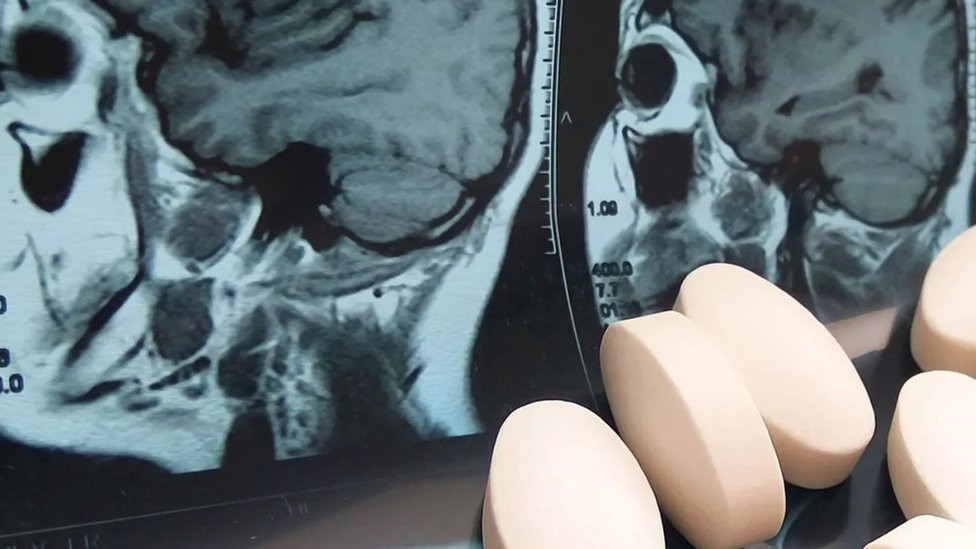

Zdravlje i medicina: Lekovi koji menjaju ono što smo

BBC | 28.01.2023.